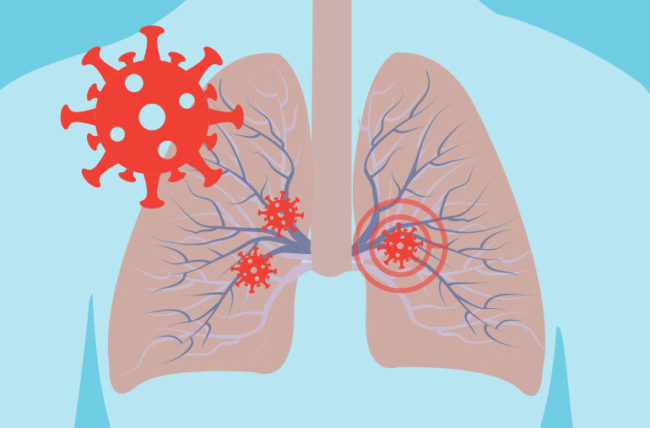

विश्व स्वास्थ्य संगठन (डब्लुएचओ) ले एक पटक ठीक भएका बिरामीमा पुनः कोभिड–१९ को संक्रमण पोजेटिभ देखिनुको पछाडि फोक्सोको मरिसकेका कोशिकाहरु जिम्मेवार हुनसक्ने बताएको छ । गत अप्रिलमा दक्षिण कोरियाका स्वास्थ्य अधिकारीहरुले १ सयभन्दा बढी कोरोनाभाइरस संक्रमितहरु ठीक भइसकेको केही समयपछि पुनः पाजेटिभ देखिएको बताएका थिए । यसपछि चीनमा पनि यस्तो मामिला बाहिर आएको थियो जसलाई कोरानाको दोस्रो लहर भनेर अनुमान गरिएको थियो । नेपालमा पनि अहिले ३ जनामा यस्तै दोहोरिएको छ ।

डब्लूएचओका प्रवक्ताले एएफपीसँग कुरा गर्दै केही बिरामीहरु क्लिनिकल्ली ठीक भए पनि टेस्टमा पोजेटिभ आएको जानकारी प्राप्त भएको बताए । ‘ताजा तथ्यांक र जानकारीको आधारमा हामी यो भन्न सक्छौँ कि यो पोजेटिभ नतिजा रि–इन्फेक्सन भएर आएको नभएर बिरामीको फोक्सोबाट बाहिर निस्किरहेको मृत्त कोशिकाहरु हुन् जुन पहिले संक्रमित भएका थिए,’ उनले भने, ‘यो बिरामीको ठीक हुने प्रक्रिया हो जसमा शरीर आफै सफाइ शुरु गर्दछ । यसलाई पुनःसंक्रमण भन्न सही हुँदैन ।’

डब्लुएचओको हेल्थ इमर्जेन्सी प्रोग्रामको हिस्सा र संक्रामक रोग महामारीकी विज्ञ मारिया वान केहोबले मृत्त कोशिकाको बारेमा सम्झाउँदै भन्छिन्, ‘जब हाम्रो फोक्सोले आफैलाई ठीक गर्न थाल्छ, तब त्यहाँ रहेको मृत्त कोशिकाहरु बाहिर आउन थाल्छन् । यी फोक्साका सुक्ष्म अंश हुन्छन् जो हाम्रो नाक र मुखको बाटो हुँदै बाहिर निस्कन्छन् । यी कोशिका संक्रामक भाइरस होइनन् । यो पुनः संक्रमण भएको पनि होइन । यो उपचार प्रक्रियाको एक हिस्सा हो । तर, के यसको कारण बिरामीले प्रतिरोधात्मक शक्ति प्राप्त गर्यो ? यसको उत्तर भने हामीसँग अहिले छैन ।’

विभिन्न अनुसन्धानबाट कोरोनाभाइरसबाट संक्रमित बिरामीको शरीरमा एक या दुई हप्तापछि एन्टिबडी बनाउन सुरु हुन्छ । त्यसपछि संक्रमणको लक्षण कम हुँदै जान्छ । तर, विज्ञहरुका अनुसार शरीरले भाइरसको नयाँ हमला सहन पर्याप्त मात्रामा प्रतिरोधात्मक क्षमता गर्छ कि गर्दैन भनेर स्पष्ट भइसकेको छैन । यो प्रतिरोधात्मक क्षमता कति समय टिक्छ भन्ने कुराको यकिन हुन बाँकी रहेको छ । अलग–अलग भाइरसको लागि प्रतिरोधात्मक क्षमता अलग–अलगत हुन्छन् । यो केही महिनादेखि लिएर जीवनभर हुनसक्छ ।